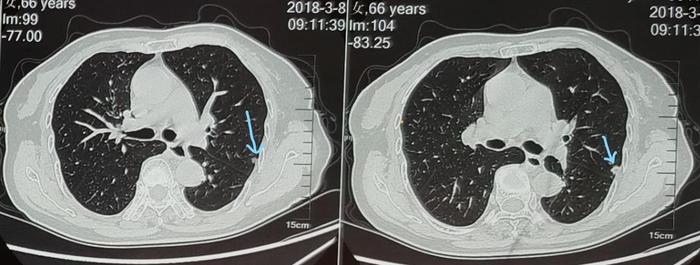

上图可见蓝色箭头指示的2018年3月左下肺混合磨玻璃结节,大小约20毫米,实性成分为主,照片上结节内部有一些发暗的的小缝隙,使这个混合磨玻璃结节看起来像一个洋葱头。这是一个混合磨玻璃结节,但是当时接诊的医生由于水平有限,认为是慢性炎症,没有认出这个结节其实是一个实性成分为主的混合磨玻璃结节。

上图可见蓝色箭头指示的2018年3月左上肺实性结节,大小约9毫米,距离肋骨处的胸膜较近。当时也认为是慢性炎症。

上图可见蓝色箭头指示的2018年3月左上肺混合磨玻璃结节,大小约10毫米,内部点状实性成分。这个结节由于影子较淡,当时被忽略掉了,没有医生看见这个结节。